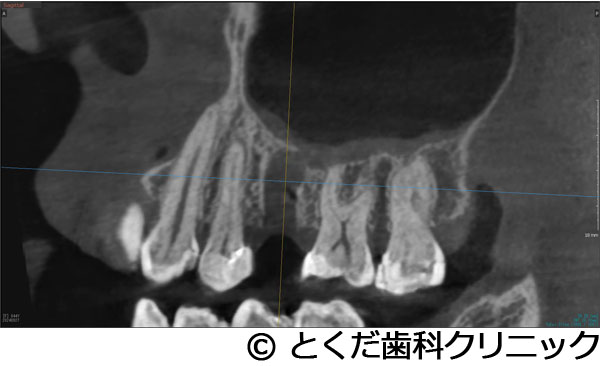

»õ²ÊÍѤΥ³¥ó¥Ó¡¼¥àCT¤Î»£±Æ¥Ç¡¼¥¿¤ä¡¢¸÷³Ø°õ¾Ý¡¢¥·¥ß¥å¥ì¡¼¥·¥ç¥ó¥½¥Õ¥È¤Ê¤É¤ò³èÍѤǤ¤ë¡¢¥³¥ó¥Ô¥å¡¼¥¿¤Ë¤è¤ë¼ê½Ñ¥¬¥¤¥É¥·¥¹¥Æ¥à¤òºÎÍѤ·¤Æ¤¤¤Þ¤¹¡£

ŬÀڤʥ¤¥ó¥×¥é¥ó¥È¤ÎËäÆþ°ÌÃÖ¤ò¥·¥ß¥å¥ì¡¼¥·¥ç¥ó¤¹¤ë¤³¤È¤¬¤Ç¤¡¢¼ê½Ñ»þ¤Ë¤â¥¬¥¤¥É¤¬¤¢¤ë¤³¤È¤Ç¡¢¼ê½Ñ»þ´Ö¤Îû½Ì¤ä¡¢Ä㿯½±¤Ç¤Î¼ê½Ñ¤¬´üÂԤǤ¤Þ¤¹¡£

¡Ú¾ÉÎã1¡Ûº¸¾å3ÈÖ4È֤˴ؤ·¤Æ¤Ï¡¢¥¤¥ó¥×¥é¥ó¥È¤Î¼ê½ÑÅöÆü¤ËÈ´»õ¤ò¹Ô¤¤¡¢¥¤¥ó¥×¥é¥ó¥ÈËäÆþ¡¢ÅöÆü¤Ë²¾»õ¤ÎÁõÃå¡£±¦¾å5È֤˴ؤ·¤Æ¤Ï¡¢´û¸¹ü3mmÄøÅÙ¤·¤«¤Ê¤¤¥±¡¼¥¹¤Ë¥°¥é¥Õ¥È¥ì¥¹¥µ¥¤¥Ê¥¹¥ê¥Õ¥È¤ò»Ü¹Ô¡£¼ê½Ñ¸å¡¢4¥õ·î¤Ç¡¢ºÇ½ªÊäÄÖʪ¤Î3¥æ¥Ë¥Ã¥È¥¸¥ë¥³¥Ë¥¢¥Ö¥ê¥Ã¥¸¤Î¼£ÎŤò½ª¤¨¤¿¾ÉÎã

- º¸¾å3ÈÖ4È֤˴ؤ·¤Æ¤Ï¡¢¥¤¥ó¥×¥é¥ó¥È¤Î¼ê½ÑÅöÆü¤ËÈ´»õ¤ò¹Ô¤¤¡¢¥¤¥ó¥×¥é¥ó¥ÈËäÆþ¡¢ÅöÆü¤Ë²¾»õ¤ÎÁõÃå¡£±¦¾å5È֤˴ؤ·¤Æ¤Ï¡¢´û¸¹ü3mmÄøÅÙ¤·¤«¤Ê¤¤¥±¡¼¥¹¤Ë¥°¥é¥Õ¥È¥ì¥¹¥µ¥¤¥Ê¥¹¥ê¥Õ¥È¤ò»Ü¹Ô¡£¼ê½Ñ¸å¡¢4¥õ·î¤Ç¡¢ºÇ½ªÊäÄÖʪ¤Î3¥æ¥Ë¥Ã¥È¥¸¥ë¥³¥Ë¥¢¥Ö¥ê¥Ã¥¸¤Î¼£ÎŤò½ª¤¨¤¿¾ÉÎã

º¸¾å3456¤Ë¥Ö¥ê¥Ã¥¸¼£ÎŤ¬¹Ô¤ï¤ì¤Æ¤¤¤¿¤¬¡¢º¸¾å5¤Î¹üµÛ¼ý¤ÈÇÓÇ¿¤òǧ¤á¤ë¤¿¤á¤ËÈ´»õ¤ò¹Ô¤Ã¤¿2¥õ·î¸å¤Ë´µ¼ÔÍͤϥ¤¥ó¥×¥é¥ó¥È¼£ÎŤò´õ˾¡£º¸¾å3¤Ë´Ø¤·¤Æ¤ÏưÍɤòǧ¤á¤Æ¤¤¤¿¤¿¤á¡¢Êݸ¤·¤Æ¤â¾ÍèŪ¤ÊÈ´»õ¤¬Í½ÁÛ¤µ¤ì¤¿¤¿¤áÈ´»õ¤ò¹Ô¤¤¡¢º¸¾å345¤Î3¥æ¥Ë¥Ã¥È¼°¥Ö¥ê¥Ã¥¸¤Î¥¤¥ó¥×¥é¥ó¥È¼£ÎŤò·×²è¡£½Ñ¸å¤Î¿³ÈþÌ̤ò¹Íθ¤·¤Æ¡¢º¸¾å3¤Î¥¤¥ó¥×¥é¥ó¥È¤Èº¸¾å4¤Î»Ã´Ö¥¤¥ó¥×¥é¥ó¥È¤òÍøÍѤ·¤¿²¾»õ¤òÆþ¤ì¤Æ¤¤¤Þ¤¹¡£º¸¾å3È֤λõÆùÂà½Ì¤òͽËɤ¹¤ë¤¿¤á¤Ë¡¢»õ¤Î°ìÉô¤ò²¹Â¸¤¹¤ë¥ë¡¼¥È¥á¥ó¥Ö¥ì¥ó¥Æ¥¯¥Ë¥Ã¥¯¤ò¹Ô¤Ã¤Æ¤¤¤Þ¤¹¡£º¸¾å5¤Ë´Ø¤·¤Æ¤Ï¡¢¾å³Ü¹ü¤¬¤«¤Ê¤êÇö¤«¤Ã¤¿¤¿¤á¡Ê´û¸¹ü3mmÄøÅÙ¡Ë¥°¥é¥Õ¥È¥ì¥¹¥µ¥¤¥Ê¥¹¥ê¥Õ¥È¤ò»Ü¹Ô¤·¤Æ¤¤¤Þ¤¹¡£ºÇ½ªÅª¤ÊÊäÄÖʪ¤Ï¥ª¡¼¥ë¥¸¥ë¥³¥Ë¥¢¤Î3¥æ¥Ë¥Ã¥È¥Ö¥ê¥Ã¥¸¤Ç¡¢À½ºî¤Ë´Ø¤·¤Æ¤Ï¡¢¥ª¡¼¥ë¥Ç¥¸¥¿¥ë¤Ç¹Ô¤Ã¤Æ¤¤¤Þ¤¹¡£

¡Ú¾ÉÎã2¡Û¤«¤Ê¤ê¾å³Ü¹ü¤¬¤Ê¤¤¡Ê¾å³Ü´û¸¹ü1.5¡Á2mm¤·¤«¤Ê¤¤¡Ë¥±¡¼¥¹¤Ç¡¢¤ï¤º¤«2¥õ·îȾ¤Ç¼£ÎŤò½ª¤¨¤¿¥±¡¼¥¹

- ¤«¤Ê¤ê¾å³Ü¹ü¤¬¤Ê¤¤¡Ê¾å³Ü´û¸¹ü1.5¡Á2mm¤·¤«¤Ê¤¤¡Ë¥±¡¼¥¹¤Ç¡¢¤ï¤º¤«2¥õ·îȾ¤Ç¼£ÎŤò½ª¤¨¤¿¥±¡¼¥¹

»õ¼þɤˤè¤ê¡¢±¦Â¦6È֤ξå³Ü¹ü¤¬µÛ¼ý¤·¤Æ¡¢1.5¡Á2mmÄøÅ٤ιü¤·¤«»Ä¤Ã¤Æ¤¤¤Ê¤«¤Ã¤¿¤¿¤á¡¢½¾Íè¤Ê¤éÂ礤ʿ¯½±¤È1ǯ°Ê¾å¤Î¼£ÎÅ´ü´Ö¤¬¤«¤«¤ë¥µ¥¤¥Ê¥¹¥ê¥Õ¥È¤¬É¬ÍפǤ¢¤Ã¤¿¤¬¡¢´µ¼ÔÍͤؤλþ´ÖŪ¡¢ÆùÂÎŪ¡¢¶âÁ¬ÅªÉéô¤¬Â礤¯¤Ê¤ë¤³¤È¤ò¹Íθ¤·¤Æ¡¢º£²ó¤Ï¡¢¥¨¥¯¥¹¥È¥é¥ï¥¤¥É¥·¥ç¡¼¥È¥¤¥ó¥×¥é¥ó¥È¤È¥Ç¥ó¥µ¡¼¥Ð¡¼¤ò»ÈÍѤ·¤¿¥°¥é¥Õ¥È¥ì¥¹¥µ¥¤¥Ê¥¹¥ê¥Õ¥È¤òÁªÂò¤·¤Æ¡¢¤ï¤º¤«¡¢2.5¥õ·î¤Ç¾åÉô¥¸¥ë¥³¥Ë¥¢¤ÎºÇ½ªÊäÄÖʪ¤òÁõÃ夷¤Æ¼£ÎŤò½ª¤¨¤Æ¤¤¤Þ¤¹¡£

¡Ú¾ÉÎã3¡Ûº¸¾å5¤ÎËË¡¦À妤ÎÂçÉý¤Ê¹ü·ç»¤¬¤¢¤ê¡¢¤«¤Ä¡¢¾å³ÜƶÄì¤Þ¤Ç3mmÄøÅ٤δû¸¹ü¤·¤«¤Ê¤¤¾ÉÎ㤬¡¢¼£ÎÅ´ü´Ö2.5¥õ·î¤Ç¼£ÎŤ¬½ª¤ï¤Ã¤¿¥±¡¼¥¹

- º¸¾å5¤ÎËË¡¦À妤ÎÂçÉý¤Ê¹ü·ç»¤¬¤¢¤ê¡¢¤«¤Ä¡¢¾å³ÜƶÄì¤Þ¤Ç3mmÄøÅ٤δû¸¹ü¤·¤«¤Ê¤¤¾ÉÎ㤬¡¢¼£ÎÅ´ü´Ö2.5¥õ·î¤Ç¼£ÎŤ¬½ª¤ï¤Ã¤¿¥±¡¼¥¹

´µ¼ÔÍͤ¬º¸¾å5¤ÎÇÓÇ¿¤ò¼çÁʤËÍ象¡¢¾Ã±ê¸å¤ËÈ´»õ¤ò´õ˾¤·¤¿¤¿¤áÈ´»õ¤ò¹Ô¤¤¤Þ¤·¤¿¡£¤½¤Î¸å¡¢´µ¼ÔÍͤ¬¥¤¥ó¥×¥é¥ó¥È¼£ÎŤò´õ˾¤·¤¿¤¿¤áÈ´»õ¸å¡¢¼þ°ÏÁÈ¿¥¤¬°ÂÄꤹ¤ë¤Î¤òÂԤäƥ¤¥ó¥×¥é¥ó¥È¼ê½Ñ¤ò¹Ô¤Ã¤Æ¤¤¤Þ¤¹¡£ÆâÍÆ¤Ï¡¢¾å³Ü´û¸¹ü¤¬Çö¤¤¤¿¤á¥°¥é¥Õ¥È¥ì¥¹¥µ¥¤¥Ê¥¹¥ê¥Õ¥È¤ÈʹԤ·¤Æ¡¢¹ü¤¬ÂçÉý¤Ë·ç»¤·¤¿Éôʬ¤Ø¤Î¹üÊäŶºÞŶÆþ¤ò¹Ô¤¤1²óË¡¤Ç¼ê½Ñ¤ò´°Î»¤·¡¢9½µ¸å¤Ë¸÷³Ø°õ¾Ý¤Ç°õ¾Ý¤ò¹Ô¤¤¡¢¥¸¥ë¥³¥Ë¥¢¤ÎºÇ½ªÊäÄÖʪ¤ò11½µ¤ÇÁõÃ夷¤Æ¼£ÎŤò´°Î»¤·¤Æ¤¤¤Þ¤¹¡£

¡Ú¾ÉÎã4¡Ûº¸¾å4È֤ϥ¤¥ó¥×¥é¥ó¥ÈÈ´»õ¨»þËäÆþ¡¢º¸¾å6È֤Ͼå³Ü´û¸¹ü1¡Á2mm¤Î¥±¡¼¥¹¤Ç¥°¥é¥Õ¥È¥ì¥¹¥µ¥¤¥Ê¥¹¥ê¥Õ¥È¤ò»Ü¹Ô º¸²¼56¤Ï·ç»¤¬Â礤¯¡¢²¼³Ü¿À·Ð¤Þ¤Ç¤Îµ÷Î¥¤¬¤Ê¤¤¥±¡¼¥¹¤Ç¡¢²¼»õÁå´ÉËãáã¤ò²óÈò¤¹¤ë¤¿¤á¤Ë¥·¥ç¡¼¥È¥¤¥ó¥×¥é¥ó¥È¤ò»ÈÍÑ ºÇ½ªÊäÄÖʪ¤Ïº¸¾å456¤Î3¥æ¥Ë¥Ã¥È¤Î¥¸¥ë¥³¥Ë¥¢¥Ö¥ê¥Ã¥¸¡¢º¸²¼56¤Ï¥¸¥ë¥³¥Ë¥¢¤ÎÏ¢·ë´§¤òÁõÃ夷¤¿¥±¡¼¥¹

- º¸¾å4È֤ϥ¤¥ó¥×¥é¥ó¥ÈÈ´»õ¨»þËäÆþ¡¢º¸¾å6È֤Ͼå³Ü´û¸¹ü1¡Á2mm¤Î¥±¡¼¥¹¤Ç¥°¥é¥Õ¥È¥ì¥¹¥µ¥¤¥Ê¥¹¥ê¥Õ¥È¤ò»Ü¹Ô º¸²¼56¤Ï·ç»¤¬Â礤¯¡¢²¼³Ü¿À·Ð¤Þ¤Ç¤Îµ÷Î¥¤¬¤Ê¤¤¥±¡¼¥¹¤Ç¡¢²¼»õÁå´ÉËãáã¤ò²óÈò¤¹¤ë¤¿¤á¤Ë¥·¥ç¡¼¥È¥¤¥ó¥×¥é¥ó¥È¤ò»ÈÍÑ ºÇ½ªÊäÄÖʪ¤Ïº¸¾å456¤Î3¥æ¥Ë¥Ã¥È¤Î¥¸¥ë¥³¥Ë¥¢¥Ö¥ê¥Ã¥¸¡¢º¸²¼56¤Ï¥¸¥ë¥³¥Ë¥¢¤ÎÏ¢·ë´§¤òÁõÃ夷¤¿¥±¡¼¥¹

´µ¼ÔÍͤϺ¸¾å¤ÎưÍɤ¬º¸¾å56¤ÎÈ´»õ¤ò´õ˾¡£¤½¤Î¸å¡¢¥¤¥ó¥×¥é¥ó¥È¼£ÎŤò´õ˾¤·¤¿¤¿¤áº¸¾å4¤Ë´Ø¤·¤Æ¤ÏÈ´»õ¨»þËäÆþ¡£º¸¾å6¤Ë´Ø¤·¤Æ¤Ï¡¢´û¸¹ü1¡Á2mm¤Ç¥¤¥ó¥×¥é¥ó¥È¼£ÎŤ¬¸·¤·¤¤¾õÂ֤Ǥ¢¤Ã¤¿¤¬¡¢¥°¥é¥Õ¥È¥ì¥¹¥µ¥¤¥Ê¥¹¥ê¥Õ¥È¤Ç¥¤¥ó¥×¥é¥ó¥ÈËäÆþ¤ò¹Ô¤¤¤Þ¤·¤¿¡£¤½¤Î¸å¡¢2¥õ·îȾ¸å¡¢ÂçÉý¤Ë¹ü¤¬·ç»¤·¤Æ¤¤¤ë²¼³Ü56¤ËÂФ·¤Æ¥·¥ç¡¼¥È¥¤¥ó¥×¥é¥ó¥È¤ò»ÈÍѤ·¤Æ¡¢²¼³Ü¿À·Ð¤Î»½ý¤òÈò¤±¤Æ¥¤¥ó¥×¥é¥ó¥ÈËäÆþ¤Î¼ê½Ñ¤ò½ª¤¨¤Æ¤¤¤Þ¤¹¡£¤½¤Î¸å2¥õ·î¸å¤Ë¸÷³Ø°õ¾Ý¤Ç°õ¾Ý¤ò¹Ô¤¤¡¢º¸¾å456¤Ï3¥æ¥Ë¥Ã¥È¤Î¥¸¥ë¥³¥Ë¥¢¥Ö¥ê¥Ã¥¸¤òÁõÃå¡£²¼º¸56¤Ë´Ø¤·¤Æ¤Ï¹ü·ç»¤¬Â礤¤¤¿¤á¡¢»õ´§Ä¹¤¬¤À¤¤¤ÖŤ¯¤Ê¤ë¤¿¤á¡¢¥¸¥ë¥³¥Ë¥¢¤ÎÏ¢·ë´§¤òÁõÃ夷¤Æ¼£ÎŤò½ª¤¨¤Æ¤¤¤Þ¤¹¡£